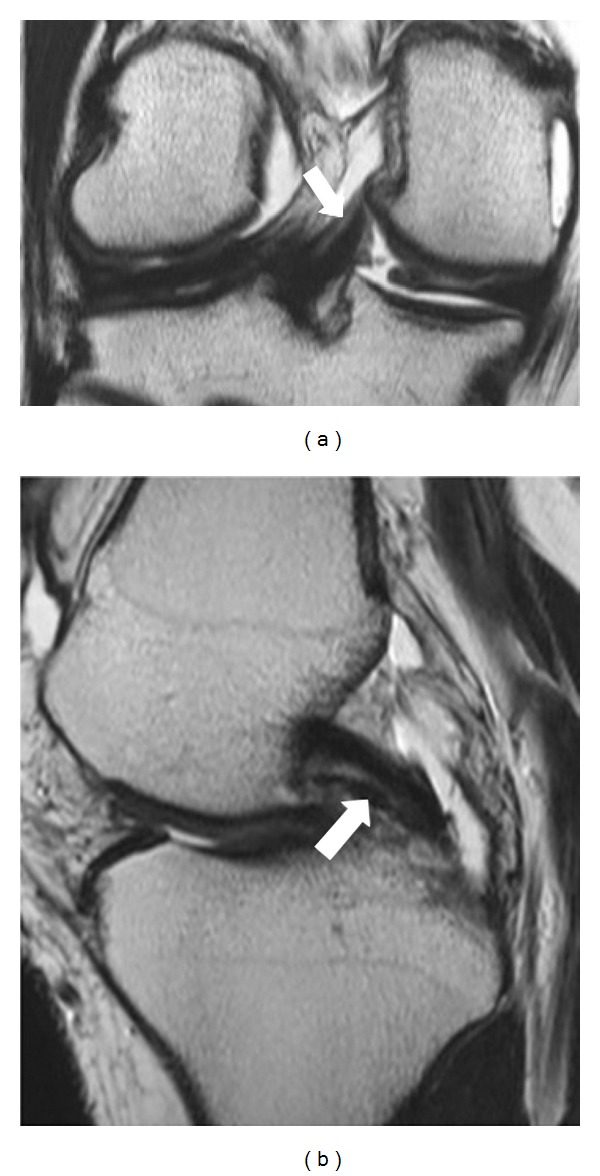

虽然半月板股骨韧带是不同的解剖单位,但从解剖学和放射学的角度来看,其解剖和功能存在争议。回顾性研究了500例膝关节MR检查,以证明其发病率和性别、年龄分布的变化,以及磁共振成像半月板股骨韧带的解剖结构。患者大多是男性,有312人,相比之下,女性患者较少,有188人。纳入这项研究的患者平均年龄为46岁。其中一半以上的人年龄在20到40岁之间;20 ~ 30岁133例,31 ~ 40岁101例,共234例。

Although meniscofemoral ligaments are distinct anatomic units, their anatomy and function are controversial from an anatomic and radiologic point of view. Five hundred knee MR examinations were retrospectively studied in an effort to demonstrate the incidence and variations regarding sex and age distribution, as well as the anatomy of the meniscofemoral ligament at magnetic resonance imaging. Patients were mostly men, three hundred and twelve, in contrast with women who were fewer, one hundred eighty-eight patients. The mean age of the patients who were included in this study was 46 years. More than half of them were between 20 and 40 years old; one hundred thirty-three patients among 20 to 30 years old and one hundred and one patients among 31 and 40 years old, in total two hundred thirty-four patients.